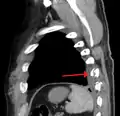

الكسر الضلعي هو كسر أو تحطم في واحد أو أكثر من العظام التي تشكل القفص الصدري. ونادراً ما يكسر الضلع الأول بسبب موقعه خلف عظم الترقوة والذي يجعله محمياً . ومع ذلك، إذا ما تم كسرها، يمكن أن تحدث أضراراً جسيمة في الضفيرة العضدية من الأعصاب والأوعية تحت الترقوة. الكسور في الضلعين الأول والثاني غالباً ما تكون مرتبطة مع إصابات في الرأس والوجه أكثر من ارتباطها بكسور في الأضلاع الأخرى. كسور الضلوع الوسطى هي الأكثر شيوعاً.[1] الكسور عادة ما تحدث من ضربات مباشرة أو غير مباشرة من إصابات السحق. أضعف جزء من الضلع هو فقط المنطقة الأمامية لزاويته، ولكن يمكن أن يحدث الكسر في أي مكان. الأضلاع الأكثر تعرضاً للكسر هي الضلع السابع والضلع العاشر. الكسور في الأضلاع السفلية قد تؤدي لمضاعفات محتملة كإصابة الحجاب الحاجز، والذي ينتج عنها فتق الحجاب الحاجز.[2] كسور الأضلاع غالباً ما تكون مؤلمة جداً لأن الأضلاع يجب أن تتحرك للسماح للتنفس. عندما يتم كسر العديد من الأضلاع في عدة أماكن ينتج عن ذلك صدر سائب، وتتحرك أجزاء العظم المنفصلة بصورة منفصلة عن باقي الصدر.

يمكن ان تحدث كسور في الاضلاع دون صدمة مباشرة، وقد سجلت حالات بعد السعال المزمن وفي مختلف الألعاب الرياضية – على سبيل المثال، التجديف، الكارتينج والغولف – غالباً ما تكون لدى نخبة من الرياضيين. ويمكن أن تحدث أيضا كنتيجة من أمراض أخرى مثل السرطان أو العدوى (الكسر المرضي). كسور هشاشة الأضلاع يمكن أن تحدث نتيجة لبنية العظام المريضة، على سبيل المثال هشاشة العظام و النقائل السرطانية المتوضعة.

معرض صور